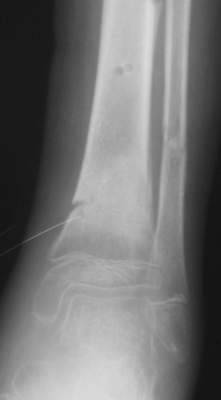

Ребенок 12 лет, поступил после падения с высоты примерно 2,5м.

Перелом костей н\3 правой голени со смещением. Перелом большеберцовой кости можно охарактеризовать как компрессионно-оскольчатый.

Скелетное вытяжение за пяточную кость.

В первые сутки значительный отек с\3, н\3голени, стопы с развитием практически неуловимого в нашей стране ;) компартмент синдрома (фасциотомии не проводилось), недочеты по укладке на скелетном

вытяжении.

Формирование некроза кожи по задней поверхности н\3 голени~ 1 %, вторичное заживление, кожная пластика. Нейропатия м\берцового нерва (отсутствие активного разгибания 1 пальца) На вытяжении около 8 нед, в дальнейшем в гипсовых повязках ~ 8 мес.

В январе 2005: варусная деформация н\3 голени, болевой с-м, комбинированная контрактура г\стопного сустава, нейропатия м\берцового нерва сохраняется слабость разгибания 1 пальца.